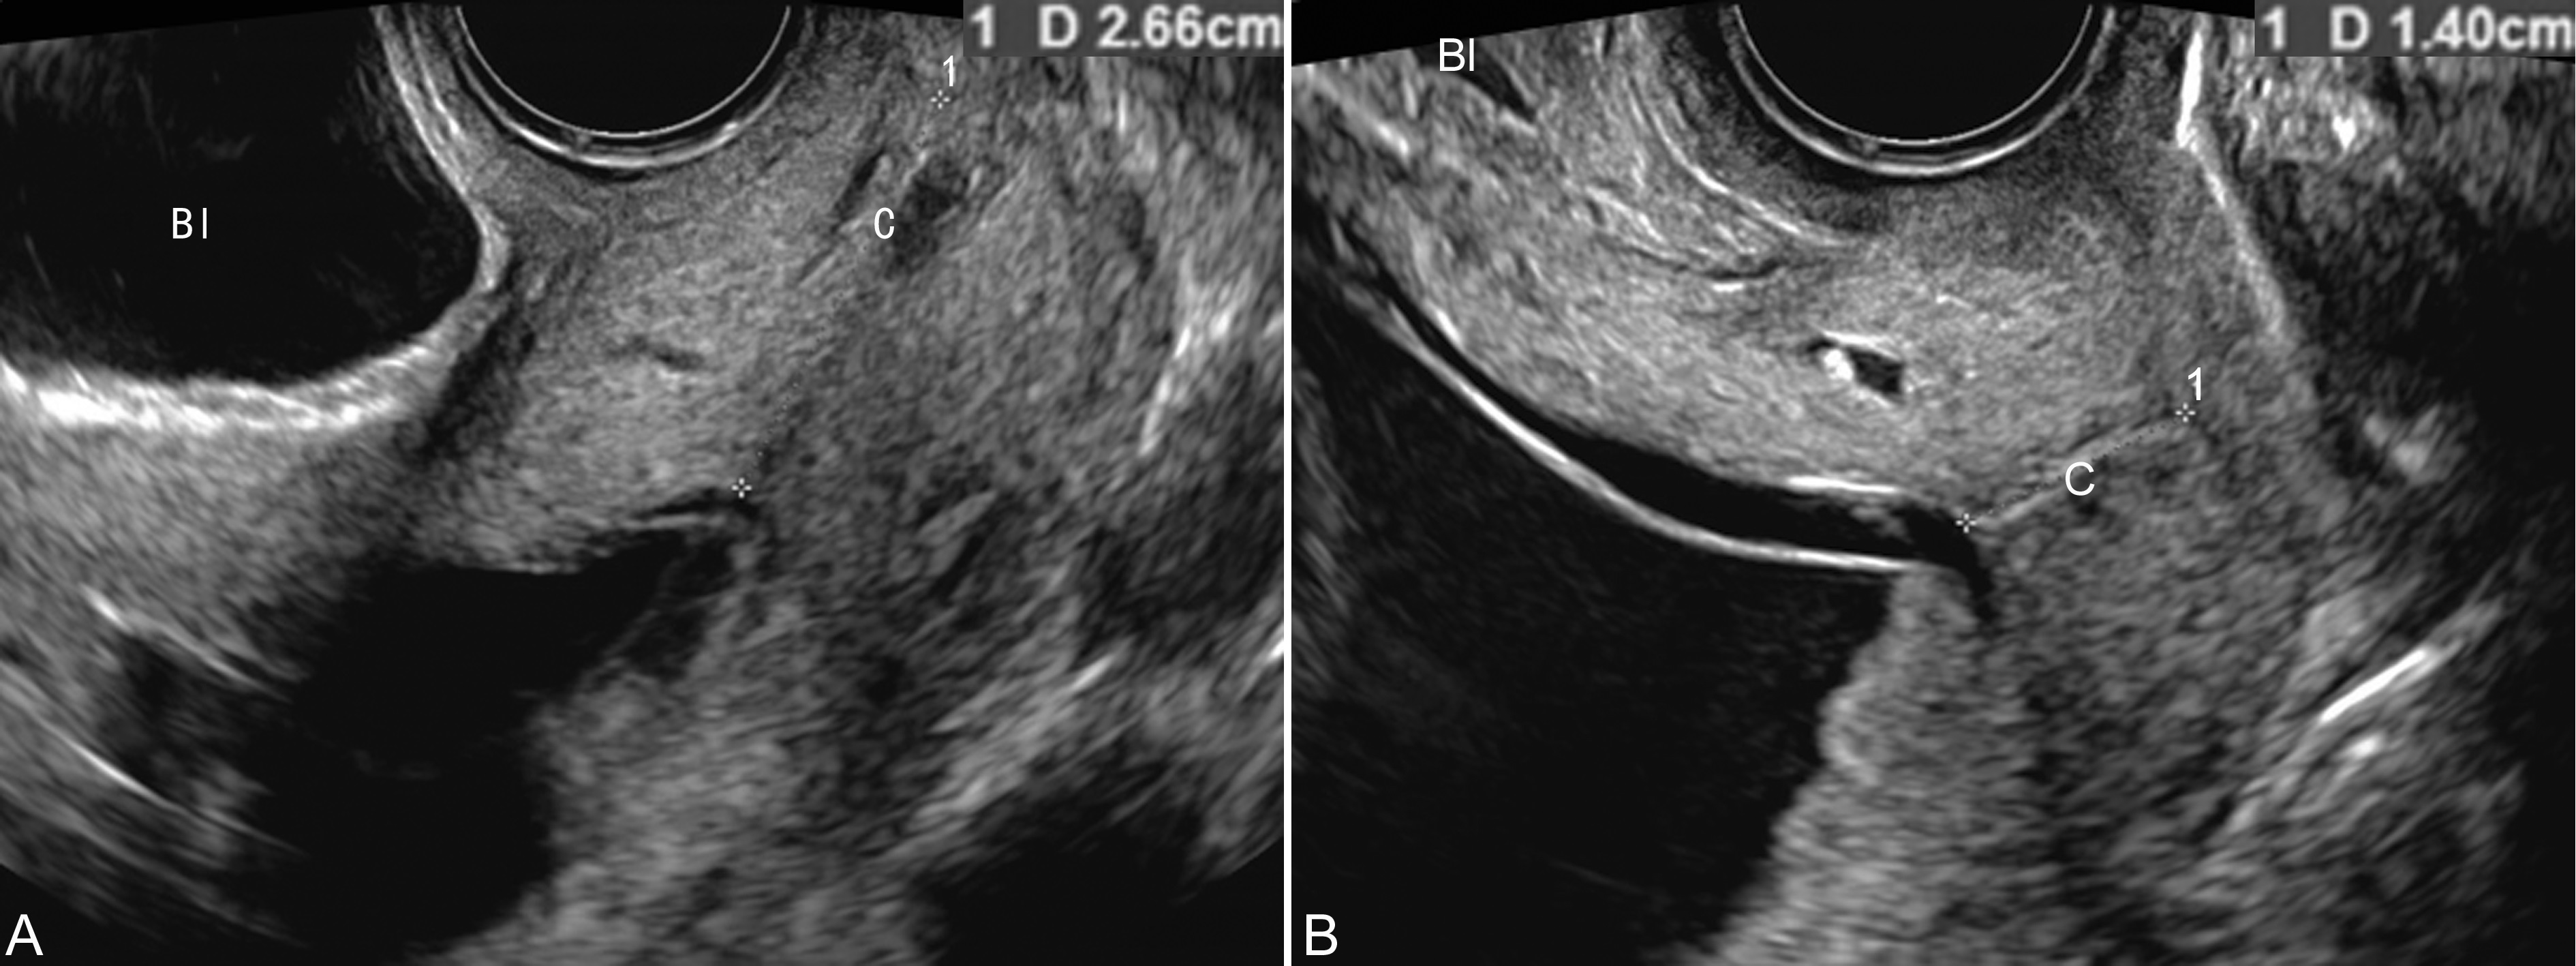

图1膀胱充盈状态对宫颈长度测量的影响

A:TVU,膀胱(Bl)充盈时测量宫颈(C)长度27mm

B:TVU,同一病人,膀胱(Bl)不充盈时测量宫颈(C)长度14mm